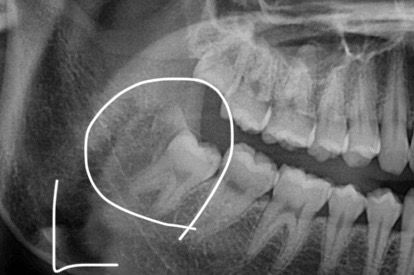

왼쪽 어금니 뒤에가 아파서 보니 뭔가 부어있는듯한게 있는데 단순염증인가요? 아니면 사랑니가 나오고 있는건가요? 왼쪽에 사랑니가 있다고 듣긴 했습니다.

이전에 찍은 엑스레이 사진도 첨부합니다.

사진에 보이는 부분은 사랑니가 매복되어 잇는 거 같습니다. 사랑니 떄문에 잇몸이 약간 튀어 나온거 같습니다.